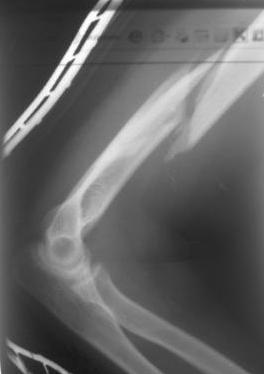

Re: Перелом н\3 плечевой кости. Тактика лечения?

Перелом нестабильный, тактика - если позволяет сосояние больной, оперативное лечение. Как пример см. ниже, можно без скобы - стяжки с ЭПФ.

Представленный способ, функциональный, данная больная в качестве внешней иммобиллизации в течение 3-х недель полльзовалась косыночной повязкой, востановление функции плеча полное. Правда травма изолированная, но операция выполнялась через три недели после травмы, тот час после обращения ко мне - иногородняя.